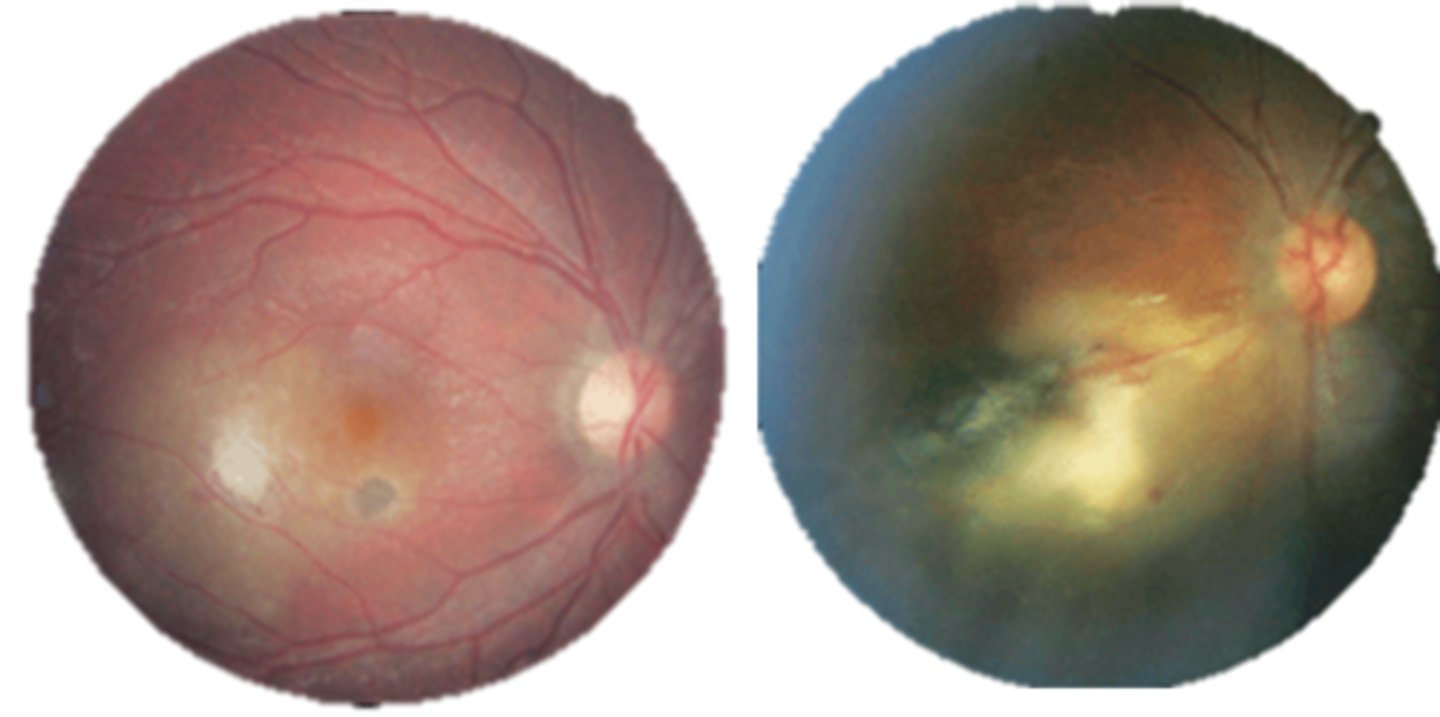

What finding of toxoplasmosis is seen in A/B?

retinitis turns into hazy scar with nerve pallor

What finding of toxoplasmosis is seen in C/D?

scarring overtime with VA loss/scotoma